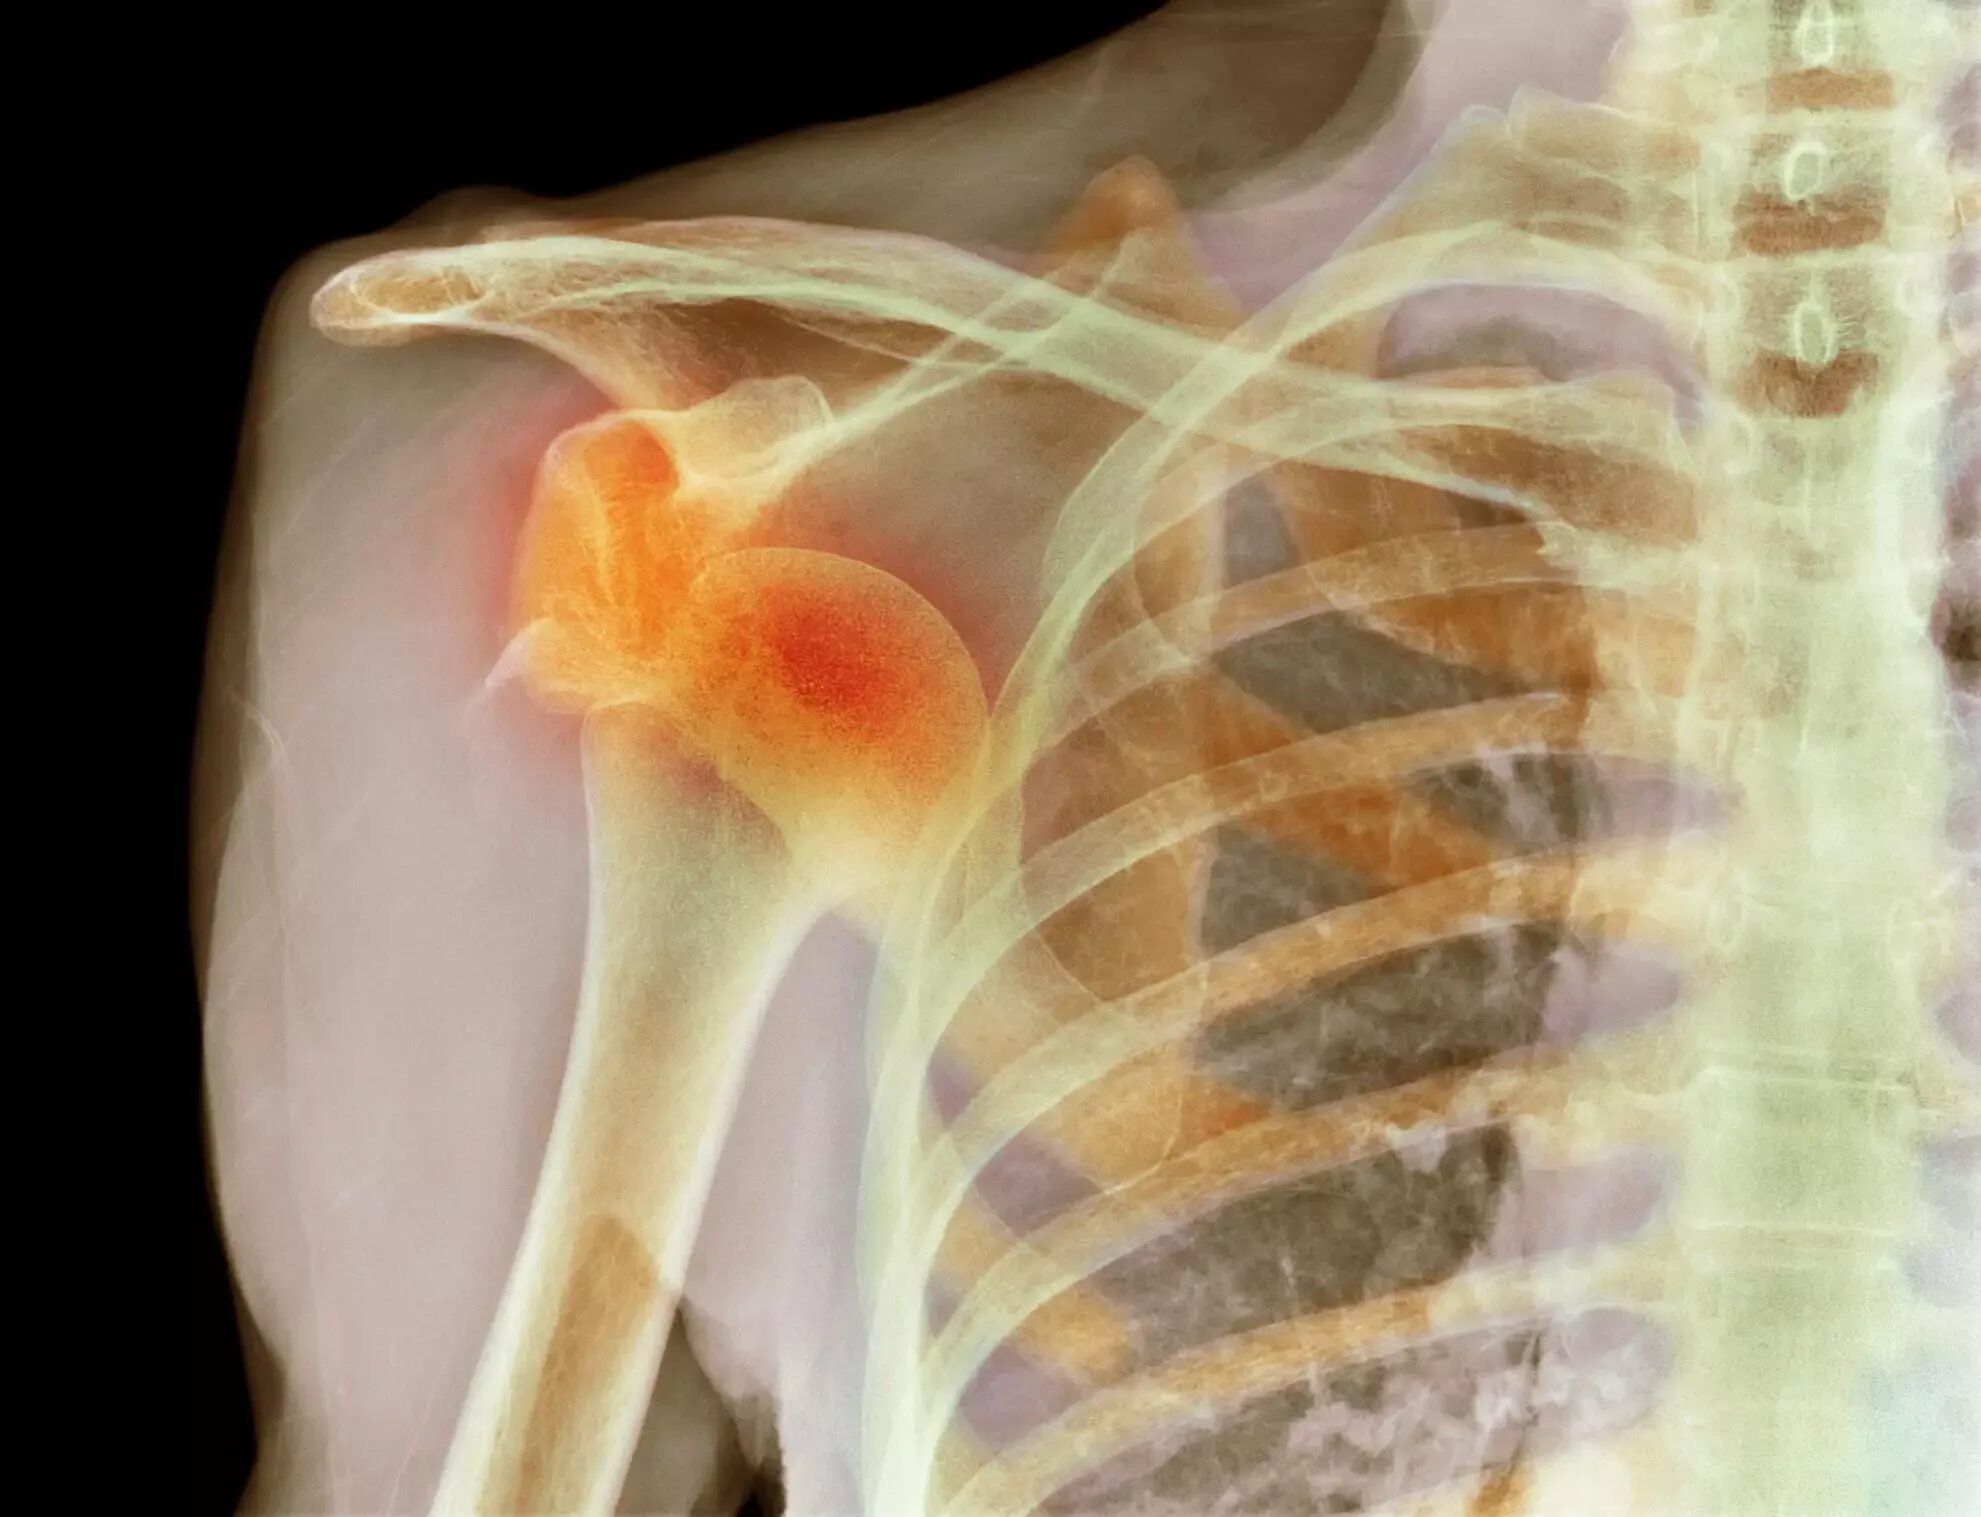

Вывих плеча вверх